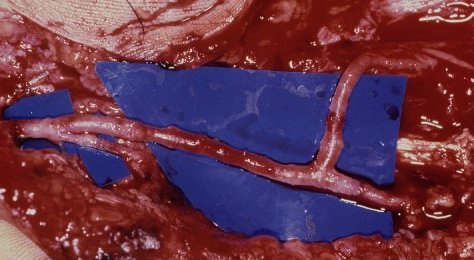

Reconstruction was performed with a branched arterial graft to the deep arch and common digital arteries, using the subscapular system as a donor site. (Case of Dr. Graham Lister)